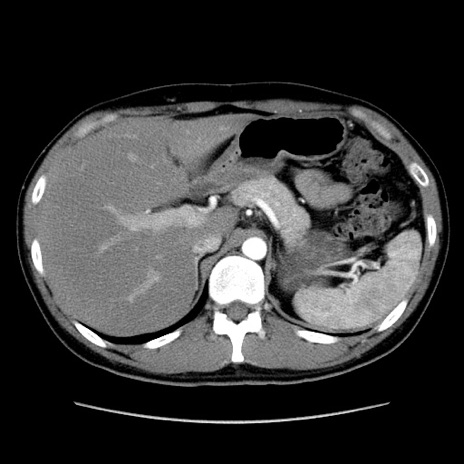

症例36(横断像)

【症例】20歳代 男性

【主訴】心窩部痛

【現病歴】今朝より上腹部痛あり。一旦軽快していたが再度出現したため救急要請。昨日夕に白身の魚を含む刺身を食べた。

【身体所見】BP 136/89mmHg、HR 74/min、BT 37.0℃、腹部:膨満、軟、心窩部に圧痛あり。反跳痛なし、筋性防御なし、腸雑音やや亢進あり。

【データ】WBC 17700、CRP 0.48